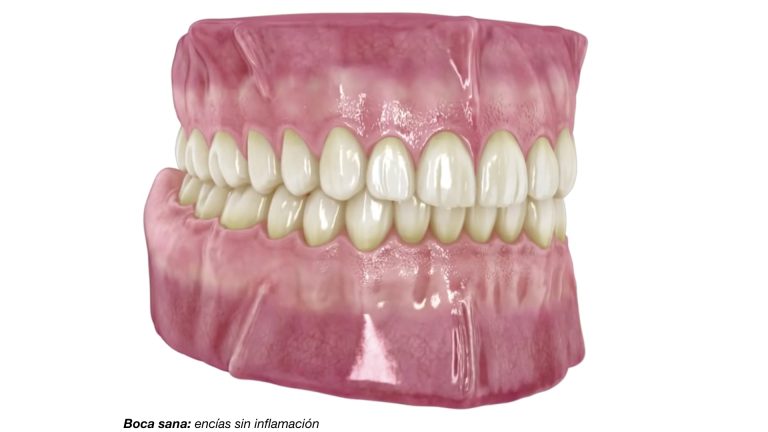

¿Es normal que me sangren las encías? Si al cepillarte los dientes notas que te sangran las encías de manera